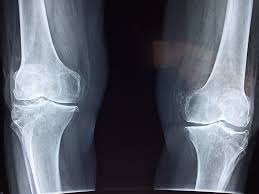

Un point souvent oublié : l’effet des sodas, surtout des colas, sur la solidité de notre ossature. Le mécanisme est fin : ces boissons prennent souvent la place d’options plus riches en calcium, comme le lait ou les boissons végétales enrichies. Pour les ados et jeunes adultes, ce remplacement met en péril la construction d’une charpente osseuse robuste. Chez les adultes, il participe à une déminéralisation lente mais constante au fil du temps.